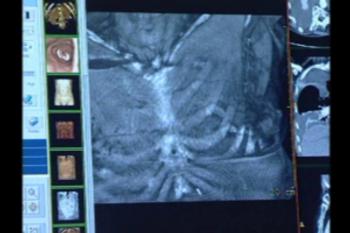

The most common chest injury identified in the study was pulmonary contusion, or bruising of the lung, occurring in 61 percent of patients. In pulmonary contusion, blood and other fluids collect in the lung tissue, potentially leading to oxygen deficiency.

Other chest injuries included pneumothorax, or collapsed lung (45 percent of patients), and rib fractures (34 percent of patients).